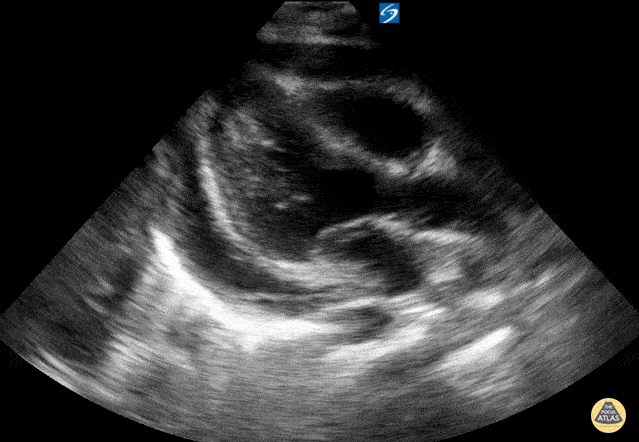

Peds-Cardiac - Moderate fibrinous pericardial effusion

Fibrinous pericardial effusion. Contributor: Peter Gutierrez, MD, FAAP, Emory University School of Medicine/Children's Healthcare of Atlanta, @pocuspete